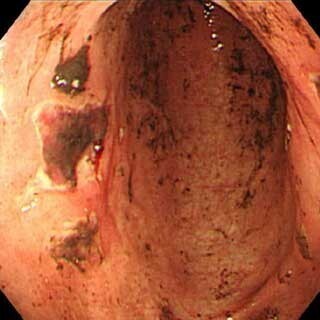

今回の研究では、心筋梗塞や脳梗塞の予防目的にLDAを長期間服用していて、小腸に3個以上の粘膜欠損を有する患者をプラセボ群とレパミド群に分け、薬剤を8週間投与した後に内視鏡検査を施行して、投与前後での粘膜欠損の完全消失率を評価した。

その結果、粘膜欠損数はプラセボ群では薬剤投与前後で差が無かったが、レバミピド群では投与後に有意に減少していたほか、粘膜欠損の完全消失率もレバミピド群がプラセボ群より約4倍高値だった。また、両群ともに薬剤投与による副作用の発症例は認められなかった。